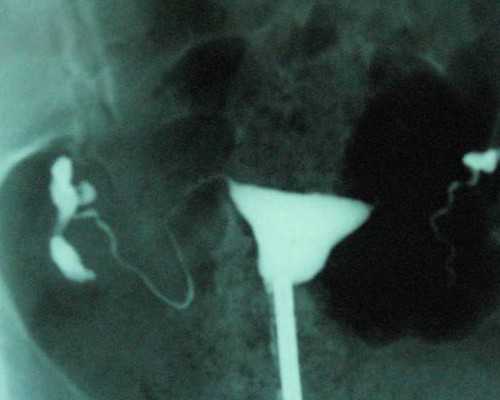

移植40天过危险期了:胎心胎芽出现后还是有胎停几率。移植40天已经有胎心胎芽也需要继续遵照医嘱服用保胎药物,同时日常饮食也要注意避免吃辛辣刺激的食物,多吃优质蛋白、富含维生素的食物,可以帮助胚胎生长发育。

试管婴儿移植后的前三个月都算是危险期,因为这个时候是胚胎发育的关键时期,稍不注意就很容易受到外界因素的干扰出现生化、胎停、流产、畸形等问题。虽然说移植40天已经有胎心胎芽,胚胎已经处于是比较稳定的状态,但是其胎盘还未形成开始发挥作用,所以还需要女性通过自身激素水平帮助胚胎生长发育,这个时候还处于危险期。